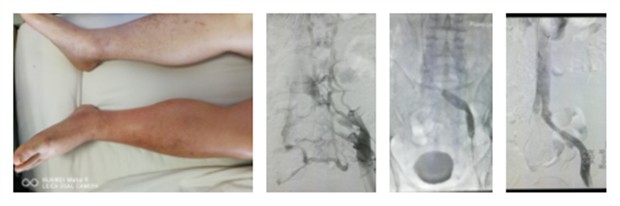

近日,我院普外科收治了这样一位患者,患者张某、男性、60岁、以“左下肢肿胀、疼痛伴活动受限20余天”之主诉入院,既往吸烟,每日三包。下肢静脉彩超未见明显血栓。那么是什么原因引起了患者下肢的肿胀、疼痛呢?普外科马建仓副主任收治患者后,依靠丰富的临床经验,以及相关检查结果,明确诊断患者为“Cokett综合症”即髂静脉受压综合征。

下肢顺行和(或)股静脉插管造影,是髂总静脉受压综合征诊断的金标准。影像特征是:受压静脉横径增宽,上粗下细,喇叭状形态;局限性充盈残缺,纤维索条和粘连结构阴影;不同程度的狭窄,如髂外静脉受压则有嵌压阴影,静脉闭塞或受压移位等影像;出现不同程度的盆腔侧支静脉;可见侧支静脉内造影剂排空延迟现象,提示髂静脉回流不畅。血管彩超和CT血管造影,可了解髂静脉的管腔及其内部血流,并了解与右侧髂总动脉、腰骶椎之间的关系,有利于诊断髂静脉压迫综合征。

通过介入手段,在髂静脉狭窄处进行球囊扩张,必要时植入支架。该方法操作简单、创伤小、成功率高。马建仓教授为该患者进行了介入手术治疗,在滤器的保护下进行了左侧髂静脉的扩张以及支架植入术,手术过程顺利,患者腹股沟区仅一个穿刺点的创伤。患者术后恢复迅速,下肢肿胀伴疼痛的症状已明显缓解,收到了非常满意的效果。